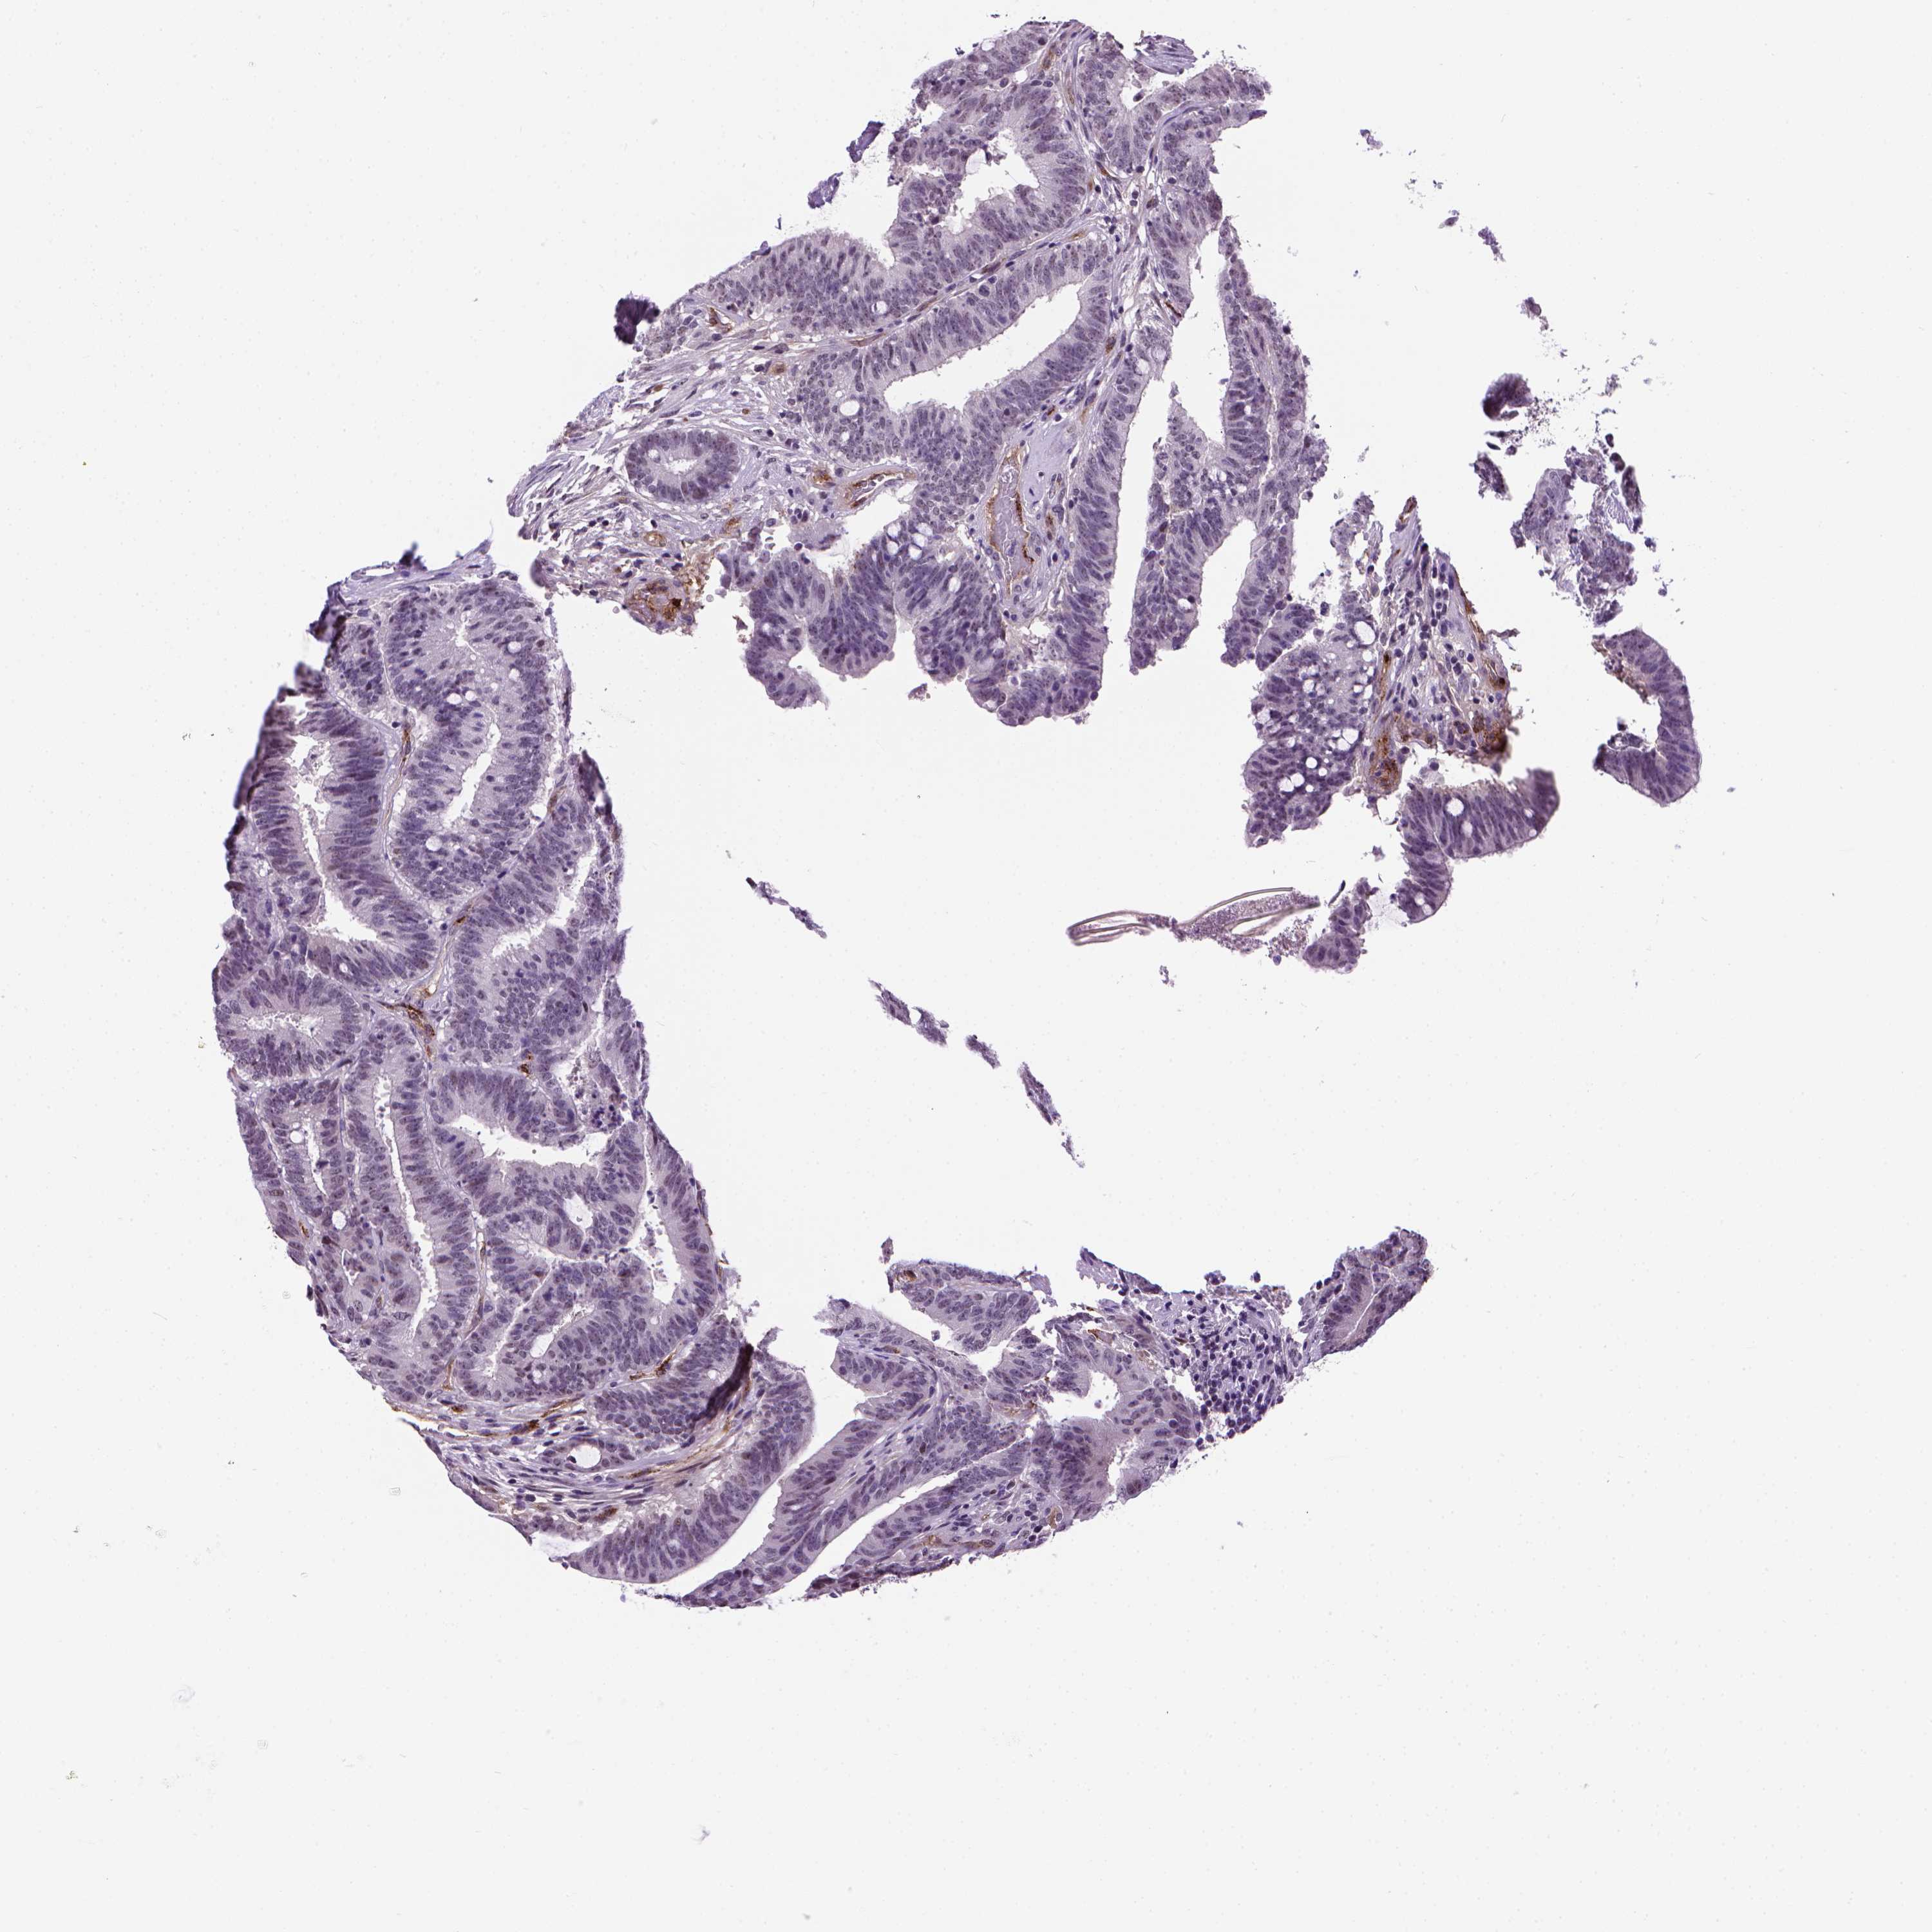

CANCER COLORECTAL CANCER Show tissue menu

COAD TCGA COAD VALIDATION READ TCGA READ VALIDATION PROTEIN COAD CPTAC PROTEIN EXPRESSION

ANTIBODIES

AND

VALIDATION